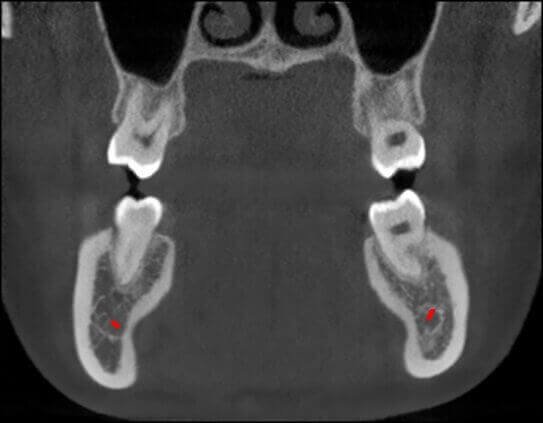

- Мощная диагностика

- Технология HR от Newtom

КОМПЛЕКСНЫЙ ГИБРИДНЫЙ КЛКТ ДЛЯ 2D/3D ВИЗУАЛИЗАЦИИ. ИЗОБРАЖЕНИЯ В ВЫСОКОМ РАЗРЕШЕНИИ С ЗАХВАТОМ МЕЛЬЧАЙШИХ ДЕТАЛЕЙ

GIANO HR – универсальное обновляемое устройство от NewTom для всех задач, связанных с радиографией. Благодаря полному диапазону опций 2D и 3D исследования для стоматологии оно предлагает множество особых трехмерных обследований для челюстно-лицевой хирургии, оториноларингологии и осмотра шейного отдела позвоночника. Визуализация только наивысшего качества с технологиями и опытом NewTom

NNT – программное обеспечение NewTom, предоставляющее несколько специальных режимов применения для имплантологии, эндодонтии, пародонтологии, челюстно-лицевой хирургии и радиографии. Это мощное технологически новейшее устройство, разработанное, чтобы снимать и обрабатывать изображения в несколько простых шагов для получения информации, необходимой для конкретного подробного диагноза пациенту. Продвинутое устройство, дающее врачу специальные инструменты для измерения анатомической области (расстояния и углы), нахождения нижнего альвеолярного нерва и замера объема верхних дыхательных путей.